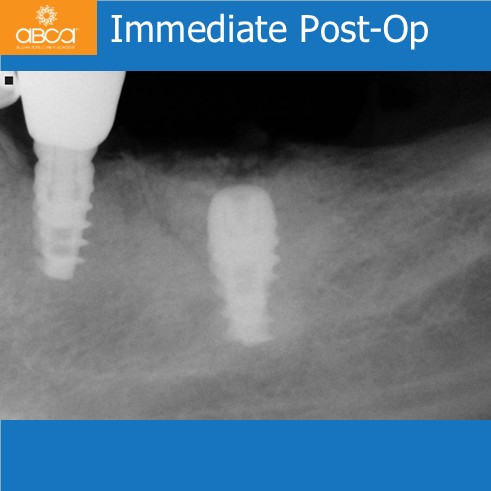

The patient presented with an infected and fractured molar with compromised buccal plate. The extraction was done in segments. Osteotomy prep grafted with Bond Apatite®, uncover osteotomy, immediate implant placement. Note the keratinized gingiva around the healed implant. The key here was no flap at the time of the extraction.